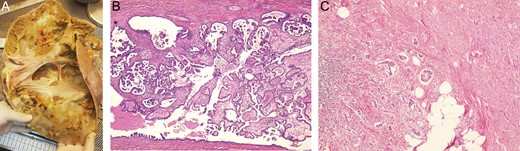

Pathology reported a giant 13 kg high-grade papillary serous ovarian cystadenocarcinoma, its capsule had multiples necrosis patches and measured 15 to 25 mm on average. It had a huge cavity that contained about four liters of a brown mucous liquid. Regretfully the tumor had an appendiceal an omental extension. (Fig. 3A–C)

(A) Tumor had macroscopically visible papillary vegetations on the inside of the cyst wall. (B) Microscopy revealed ovarian stroma with atypical cells. (C) Appendiceal wall, invaded by atypical cells ovarian tissue.